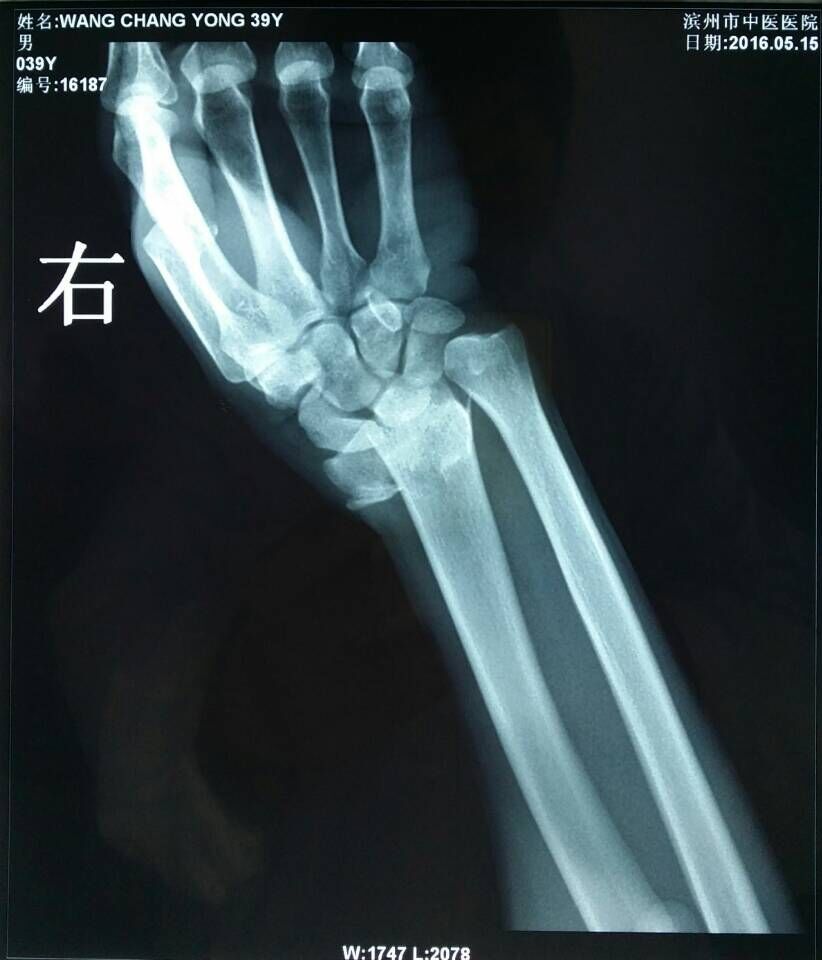

患者王某,男,39岁,踢足球时摔伤右腕关节,右腕部肿胀疼痛、活动受限2小时来我院骨伤科就诊。骨伤科刘陆勇大夫及时安排患者进行X片拍照,X-ray片(图1,2)示:右桡骨远端骨折,远端向桡侧、背侧移位,近端向掌侧移位,右端尺骨茎突骨皮质不连续,见游离骨片影,初步诊断为“桡骨远端骨折”。在确定骨折损伤程度后,刘陆勇大夫和杨晓晓大夫采用中医传统整复手法,给予患者行手法整复石膏外固定,整复后患者再次行x-ray检查(图3,4),x线片显示复位情况良好,效果显著。此次治疗使患者避免切开手术及二次手术取内固定的痛苦,最大限度地减轻了病人的经济负担,受到了病人的一致好评。